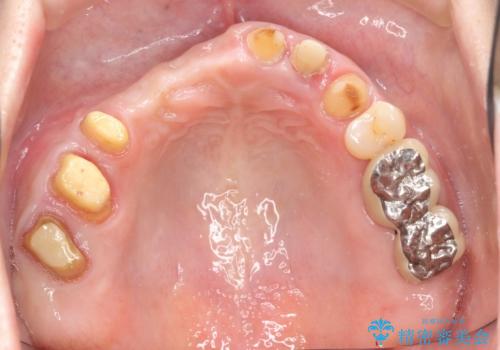

咬合性外傷による歯槽骨吸収 ブリッジ補綴

- 歯が揺れしっかりとものが噛めないことの改善を求めて来院されました。

保存の難しい歯の抜歯、保存できる歯の歯周病治療、欠損部位の歯槽堤形態回復を含めブリッジによる安定した咬合機能回復を計画します。